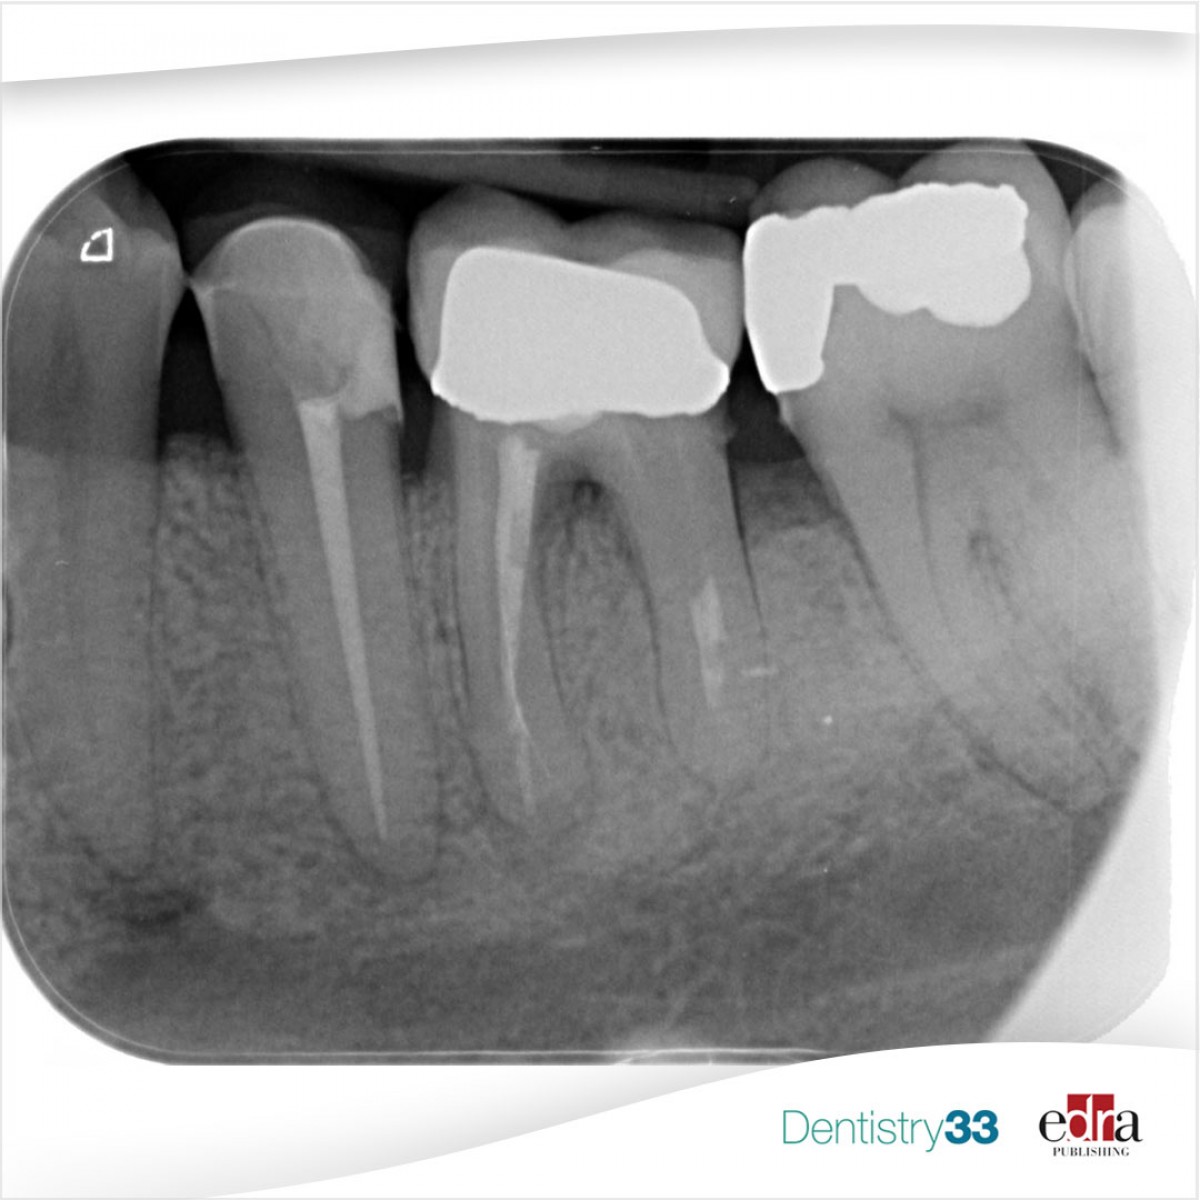

Introduction: Natural teeth can undergo structural compromissions as a result of caries, fractures and severe wear. In a recent clinical article, Fichera G. et al. introduced a comprehensive, clinically relevant novel classification of structurally compromised teeth (SCT) based on the status of the residual coronal structure and the most apical location of the residual cervical structure, with respect to periodontal tissues.

Materials and methods: To classify the SCT, standardize the overall preoperative evaluations and determine the biological and mechanical features, authors analyzed various aspects regarding the structure of the tooth and soft tissues. A classification of the coronal and cervical tooth defects, an attentive analysis of the biomechanical and biological characteristics of SCT was presented.

Results/discussion: According to the position of the most apical part of the cervical structure with respect to the gingival margin, gingival sulcus, supracrestal tissue attachment and bone crest, five major different clinical scenarios can be individuated. Within this classification, the authors intend to draw the attention to those challenging clinical situations that can pose clinicians in front of the decision on whether to intervene with direct restorative approaches or refer to more aggressive or time-consuming interventions.

Conclusions: The SCT classification is intended to enhance the existing and offer new standardized operative guidelines, enlarge the spectrum of strategical clinical options for the maintenance of the natural tooth and perform a risk-benefit analysis during diagnostic phases.